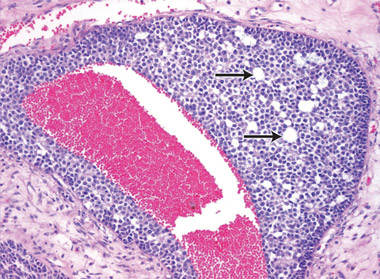

At 59 years of age, a laparotomy was performed and the patient was found to have a large left adnexal mass (Box 1, A) and a normally formed uterus. The mass was removed and a subtotal hysterectomy performed as there was no distinct lower margin of the cervix (Box 1, B). The patient was informed of the operative findings and the diagnosis of intersex. Peripheral blood karyotyping showed a 46,XY genotype. The histopathology of the gonadal tumour showed a sex cord-stromal tumour of indeterminate differentiation (Box 2). The histopathology of the uterus showed simple endometrial hyperplasia. The patient was treated with postoperative chemotherapy, but died 18 months later.

The risk of malignancy in dysgenetic gonads is significantly increased in some patients with DSD.8 The presence of the SPY gene on the GBY region of the Y chromosome is a prerequisite for malignant transformation.9 Tumours can arise in any of the gonadal cells or their precursors.8 Precursor lesions for the development of cancers occur as carcinoma-in-situ in testicular tissue and gonadoblastoma in undifferentiated gonadal tissue. A number of malignant tumour types may occur in dysgenetic gonads.8,10 These include germ cell tumours and sex cord-stromal tumours. Patients presenting with abdominal tumours in dysgenetic gonads in adulthood provide histopathologists with complex diagnostic dilemmas. Histopathological examination of the tumour in our case showed mixed elements, with cells resembling ovarian follicles, testicular tunica, granulosa cells, Sertoli cells and Leydig cells. No germ cell components were identified. The final consensus was a diagnosis of malignant sex cord-stromal tumour of indeterminate differentiation.

We thank Peter Russell of Douglass Hanly Moir Pathology for assisting with the interpretation of the histopathology results, and with the preparation of the microscopic illustrations.